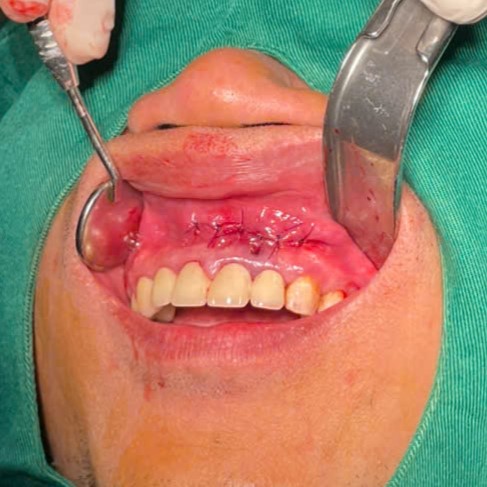

– Đường rạch có thể hình vợt, hình thang hoặc ngách lợi. Bóc tách vạt niêm mạc màng xương bằng cây bóc tách (Hình 12).

– Dùng mũi khoan Carbuatungsten tạo nhiều lỗ liên tiếp theo chu vi cửa sổ xương. Sau đó mở cửa sổ xương bằng mũi khoan hoặc cây đục xương dọc theo các lỗ đã khoan trước. Mở rộng cửa sổ bằng kìm gặm xương hoặc mũi khoan hình quả trám cho tới khi đạt kích thước cần có và bờ xương đủ dày cứng.

– Dùng curet bóc tách nang. Dùng curet cỡ lớn nhất có thể để tránh làm

thủng vỏ nang.

– Cắt cuống răng đến sát đáy nang bằng mũi khoan, sau khi đã hàn kín ống tủy.

– Kiểm tra kỹ ổ xương, làm nhẵn bờ xương, bơm rửa bằng nước muối sinh lý.

– Đặt lại vạt niêm mạc màng xương và khâu phục hồi bằng chỉ nilon.

Gây tê tại chỗ

Mở vạt bộ lộ nang, bóc tách nang

Bơm rửa kỹ bằng dung dịch nước muối sinh lý pha với betadine sau khi bóc tách loại bỏ hết nang, tổ chức viêm